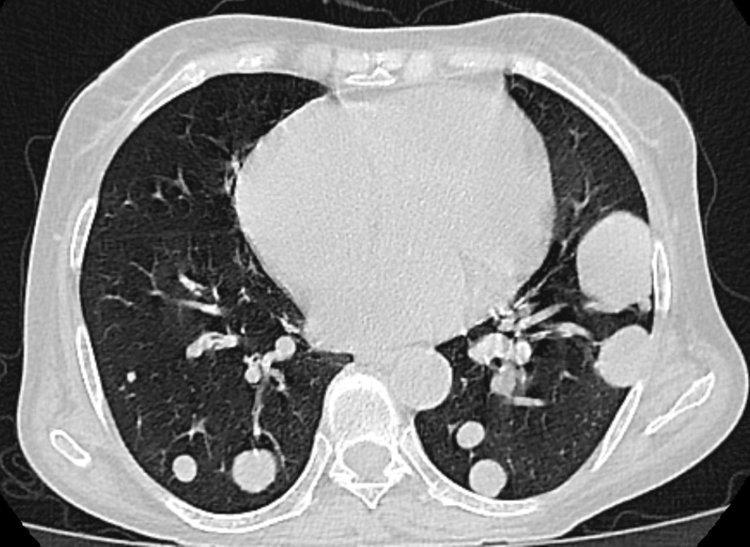

去年的體檢報告上,顯示有肺部結節,醫生叮囑他要隔段時間來複查,但他沒放在心上,覺得自己身體沒問題。

近段時間被頻繁的咳嗽、胸痛困擾,劉叔只好去了醫院,結果發現之前的結節變大了,醫生便趕緊給他安排了手術,病理顯示浸潤性腺癌,好在發現及時並處理了。

結節其實是人體內體積較小的一種腫物,可發生於人體的任何部位,由於如今的CT分辨率越來越高,因此結節的檢出率也變高了。